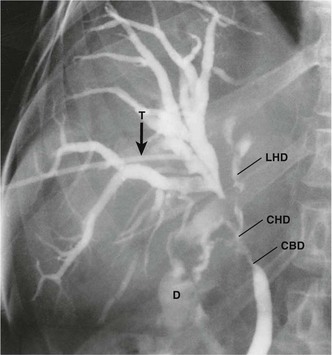

When there is obvious widespread disease, the patient should be allowed to die with minimal surgical interference but with careful attention to symptom control. Good analgesia is fundamental; severe pain can often be relieved by permanent coeliac ganglion blockade, performed percutaneously. Obstructive jaundice can usually be relieved by inserting a biliary stent at ERCP. If unsuccessful, a percutaneous transhepatic cholangiogram (PTC) can help pass a guide-wire to the duodenum to facilitate ERCP or else place a stent from above; techniques are illustrated in Figure 24.3. Surgical bypass (usually a ‘triple bypass’, see Fig. 24.3) may provide longer-lasting relief from jaundice and duodenal obstruction than stenting. Duodenal obstruction alone can be bypassed by endoscopic stent placement or laparoscopic gastroenterostomy.

Cholangiocarcinomas have a dense fibrous stroma and grow along ducts rather than producing focal proliferative lesions. The resulting smooth elongated stricture can be demonstrated by ERCP, MRCP or transhepatic cholangiography (see Fig. 24.5). Histological proof of malignancy may be elusive owing to the fibrous nature of the tumour. Unlike pancreatic cancer, cholangiocarcinomas are often slow-growing and metastasise late. Despite this, lymph node involvement at presentation is common, and extension along bile ducts and involvement of portal vein and hepatic arterial branches results in a low operability rate and an even lower long-term survival. Radical procedures combining partial hepatectomy with excision of the involved biliary tree and ‘en bloc’ portal vein resection and reconstruction may offer better clearance and improved survival for selected patients.

Primary sclerosing cholangitis (PSC) is a rare condition, probably of autoimmune origin, causing progressive fibrosis and multiple biliary strictures. Luminal narrowing causes gradual and progressive obstructive jaundice and, later, secondary cirrhosis. It may arise sporadically but often occurs in longstanding ulcerative colitis. Bile duct stenosis is usually diffuse, with a characteristic ERCP appearance (see Fig. 24.7), but just occasionally it is localised to the extrahepatic biliary system. Here the radiological appearance is indistinguishable from cholangiocarcinoma, causing a diagnostic predicament. Management is by endoscopic dilatation of clinically significant strictures and prescribing choleretic drugs to improve bile flow. In advanced cases, liver transplantation is an option; interestingly, up to a third demonstrate cholangiocarcinoma in the excised liver.